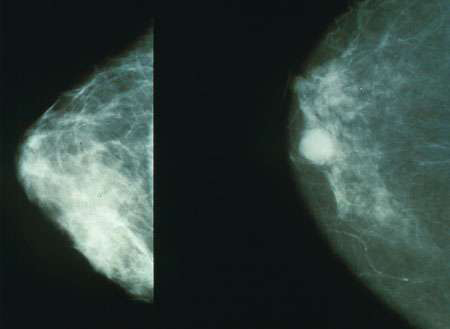

Old  Default Phương pháp điều trị ung thư vú mới nhất của Mỹ: Bỏ đói tế bào ung thư

Các nhà khoa học Mỹ tại ĐH Thomas Jeffferson sau khi nghiên cứu và quan sát thấy tế bào ung thư vú đốt năng lượng. Từ đó họ tìm ra liệu pháp mới để chữa trị bệnh ung thư đang giết hàng triệu phụ nữ. Đó là phương pháp bỏ đói tế bào ung thư vú.

Nhóm nghiên cứu đã khảo sát một dạng protein mà họ từng biết có thể thay đổi cơ chế chuyển hóa của tế bào ung thư. Protein TIGAR làm giảm khả năng tạo ra năng lượng trong quá trình sinh - hóa học thông thường là chuyển đường thành năng lượng. Sau hàng loạt thử nghiệm trên cơ thể chuột và trên tế bào, nhóm nghiên cứu phát hiện tế bào ung thư vú với lượng TIGAR ở mức độ cao thì hung hăng hơn và tăng trưởng nhanh hơn so với tế bào có lượng TIGAR bình thường. Với áp lực của TIGAR, cơ chế chuyển hóa của tế bào ung thư thay đổi và tùy thuộc vào ti thể để sản sinh năng lượng.

Trưởng nhóm nghiên cứu, TS Martinez-Outschoorn, giải thích: “Với thực tế cho thấy 70%-80% ca ung thư vú có mức độ TIGAR tăng cao mang đến cơ hội mới. Hiện đã có liệu pháp ngăn chặn cơ chế chuyển hóa của ti thể mà chúng ta có thể áp dụng để bỏ đói tế bào ung thư vú”.

Khi nhóm nghiên cứu sử dụng các loại thuốc nêu trên, họ nhận thấy mức độ ác tính của ung thư giảm sút. Sắp tới, họ sẽ thu thập và phân tích số liệu về khối u của bệnh nhân để ghi nhận hiệu quả chắc chắn của thuốc này lên khối u ung thư.